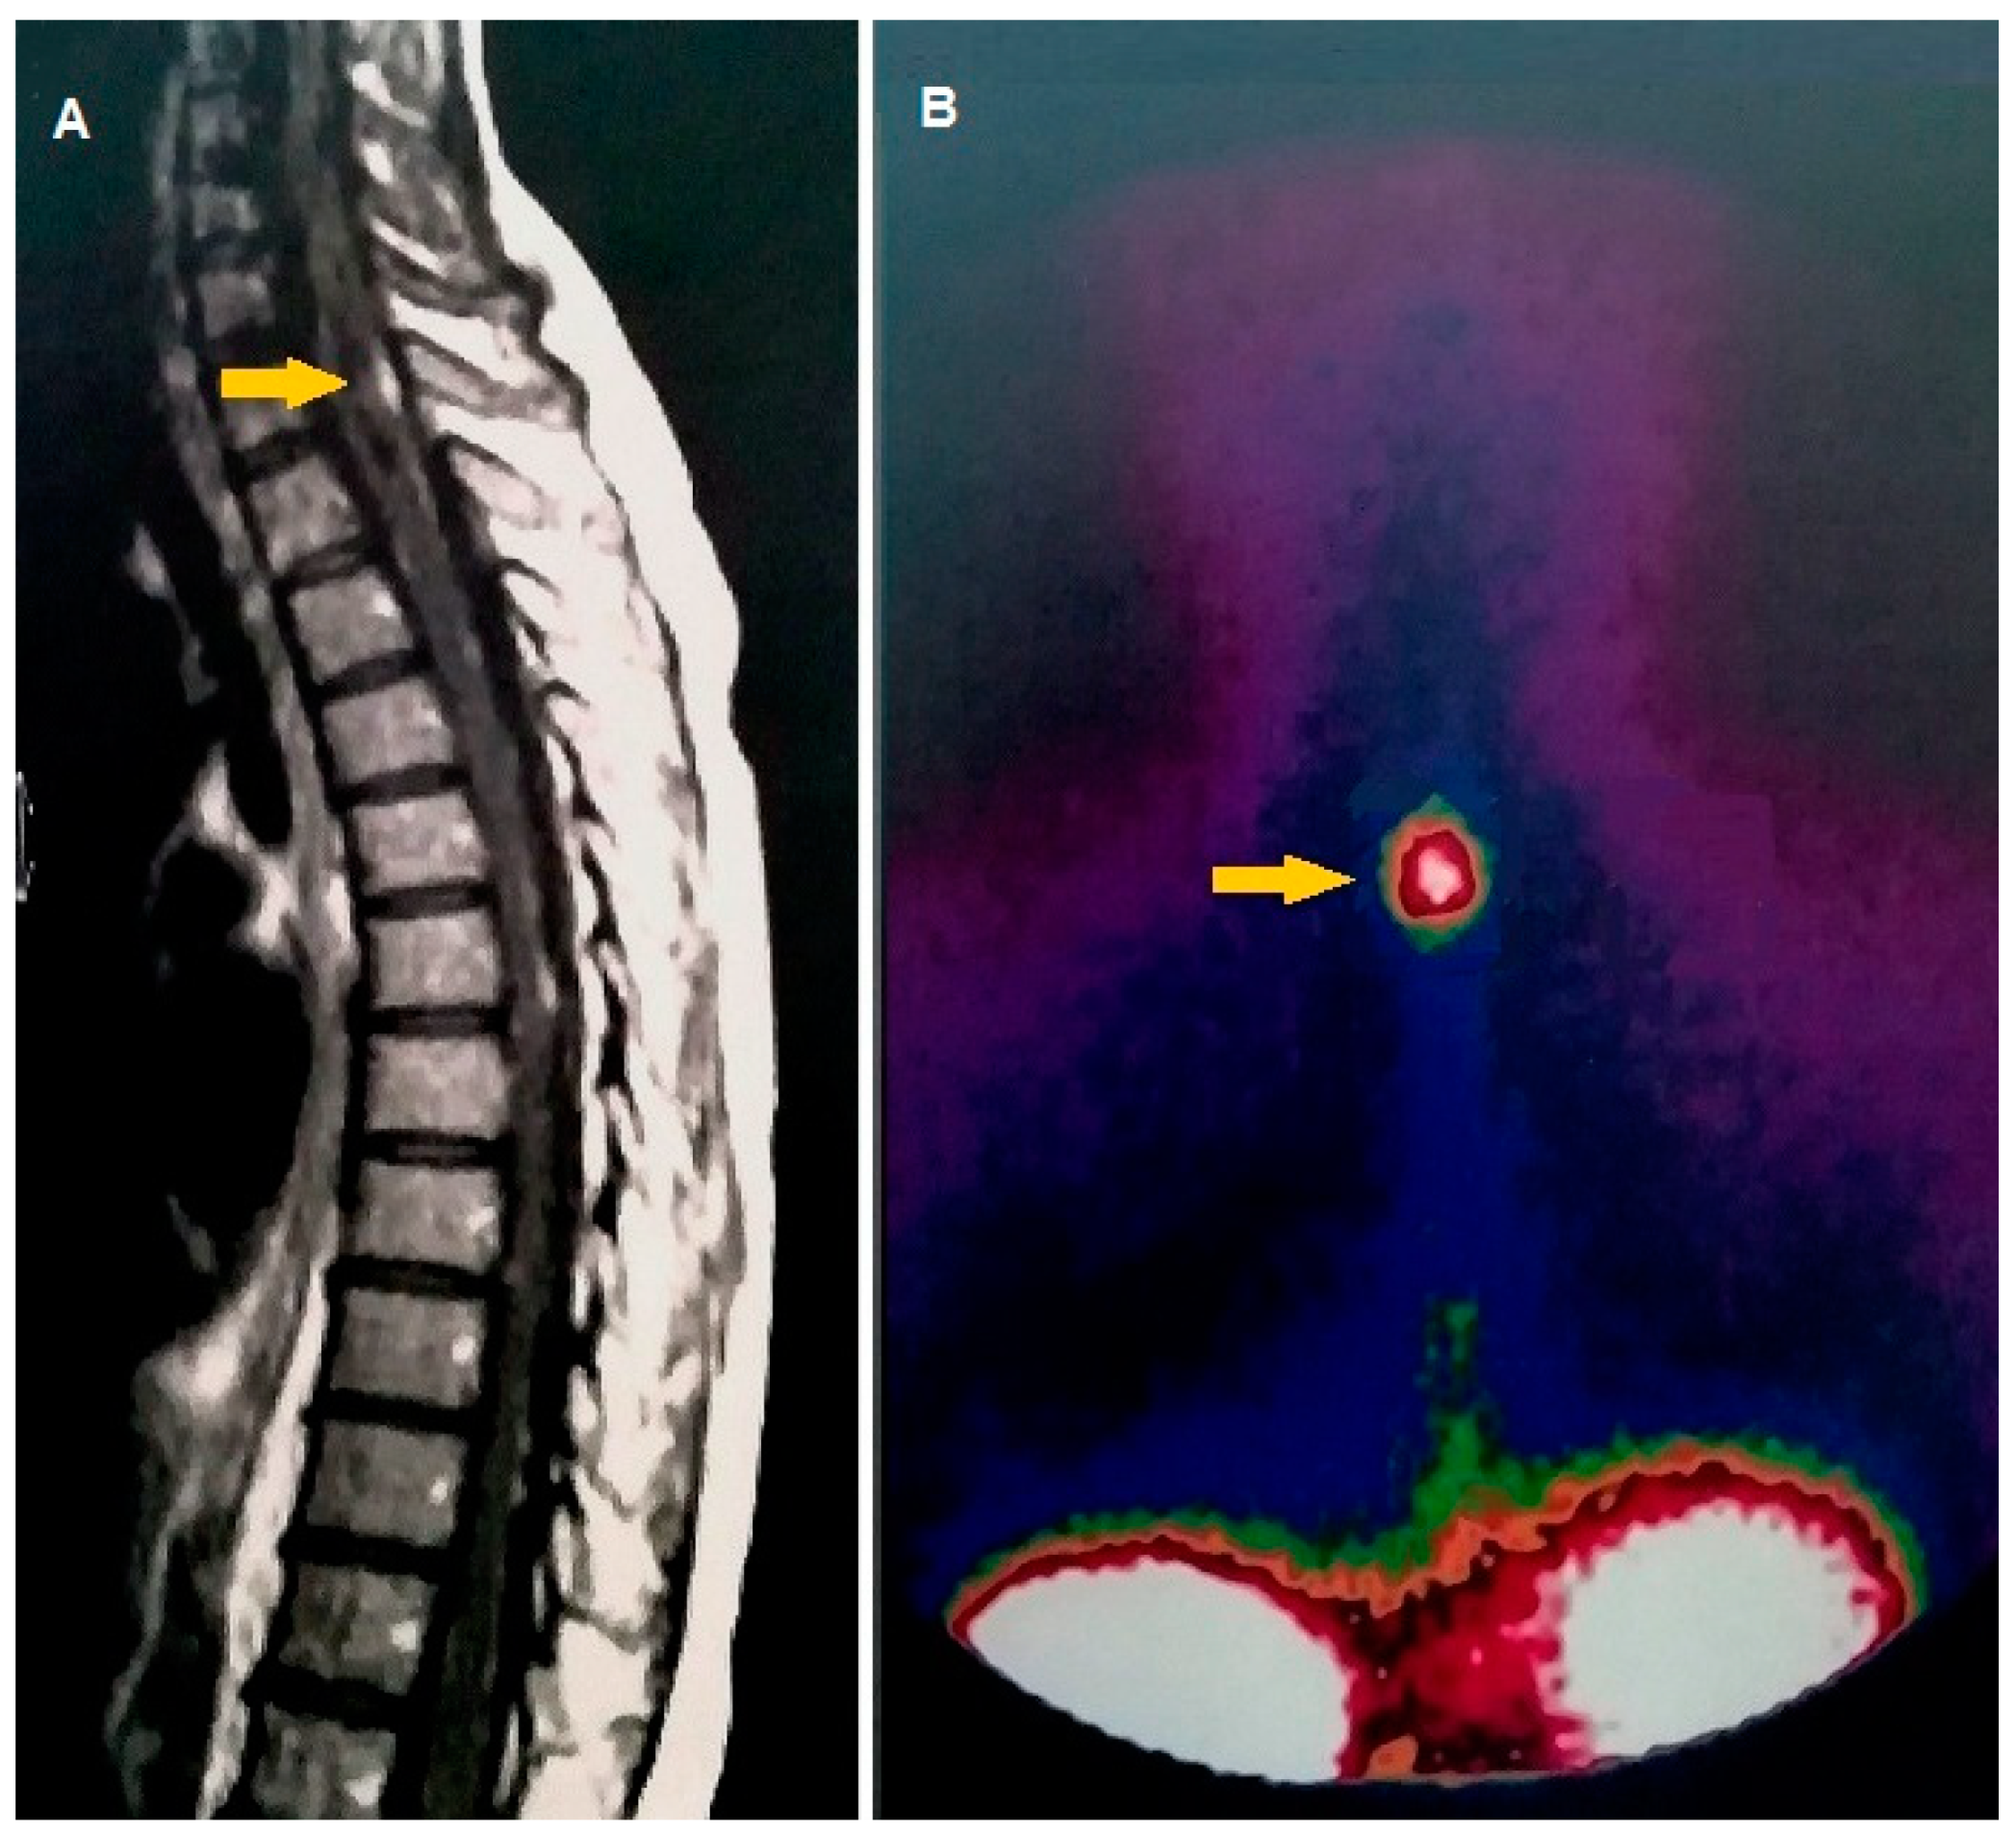

- Tscherpel, C.; Dunkl, V.; Ceccon, G.; Stoffels, G.; Judov, N.; Rapp, M.; Meyer, P.T.; Kops, E.R.; Ermert, J.; Fink, G.R.; et al. The use of O-(2-18F-fluoroethyl)-L-tyrosine PET in the diagnosis of gliomas located in the brainstem and spinal cord. Neuro-Oncology 2017, 19, 710–718. [Google Scholar] [CrossRef] [PubMed]

| Tscherpel at al. [45] | 2017 | [18F] FET | Case series | Pre-operative imaging | N = 36 | Added-value of FET PET in the brainstem and spinal cord glioma, particularly when MRI is equivocal | Mixed |